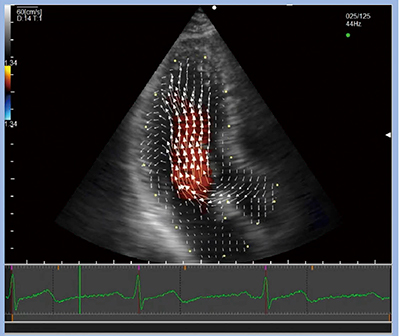

VFMは,2Dカラードプラ法とスペックルトラッキング法から血流速度を計算し,可視化する手法である。測定方法は非常にシンプルで,VFMの解析ボタンを押し,心臓壁のトレースを行うことにより,自動で各心拍でトラッキングを行い,10秒ほどで自動解析が行われる。VFMの表示方法にはさまざまなものがあり,速度ベクトル表示(図1)のほか,エネルギー損失や渦の大きさ・位置・速さ,相対的圧較差,シアストレスなど,多数のパラメータを計測することができる(図2)。

図1 VFMの解析結果:速度ベクトル表示